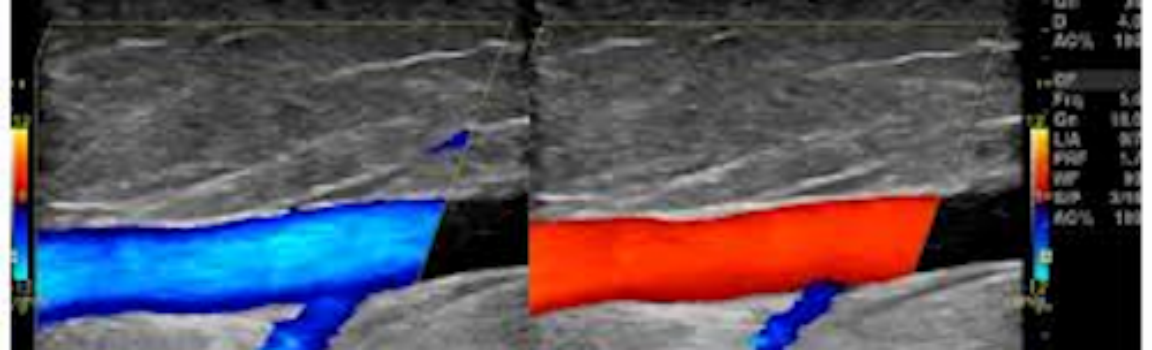

ANGIOLOGIA ECODOPPLER

Angiologia clinica e Chirurgia Vascolare con esecuzione di esami Ecocolordoppler di tutti i distretti, compresi gli organi come Fegato, Reni, Tiroide, Mammella.

Video diagnosi vascolare

Video arterioso e venoso